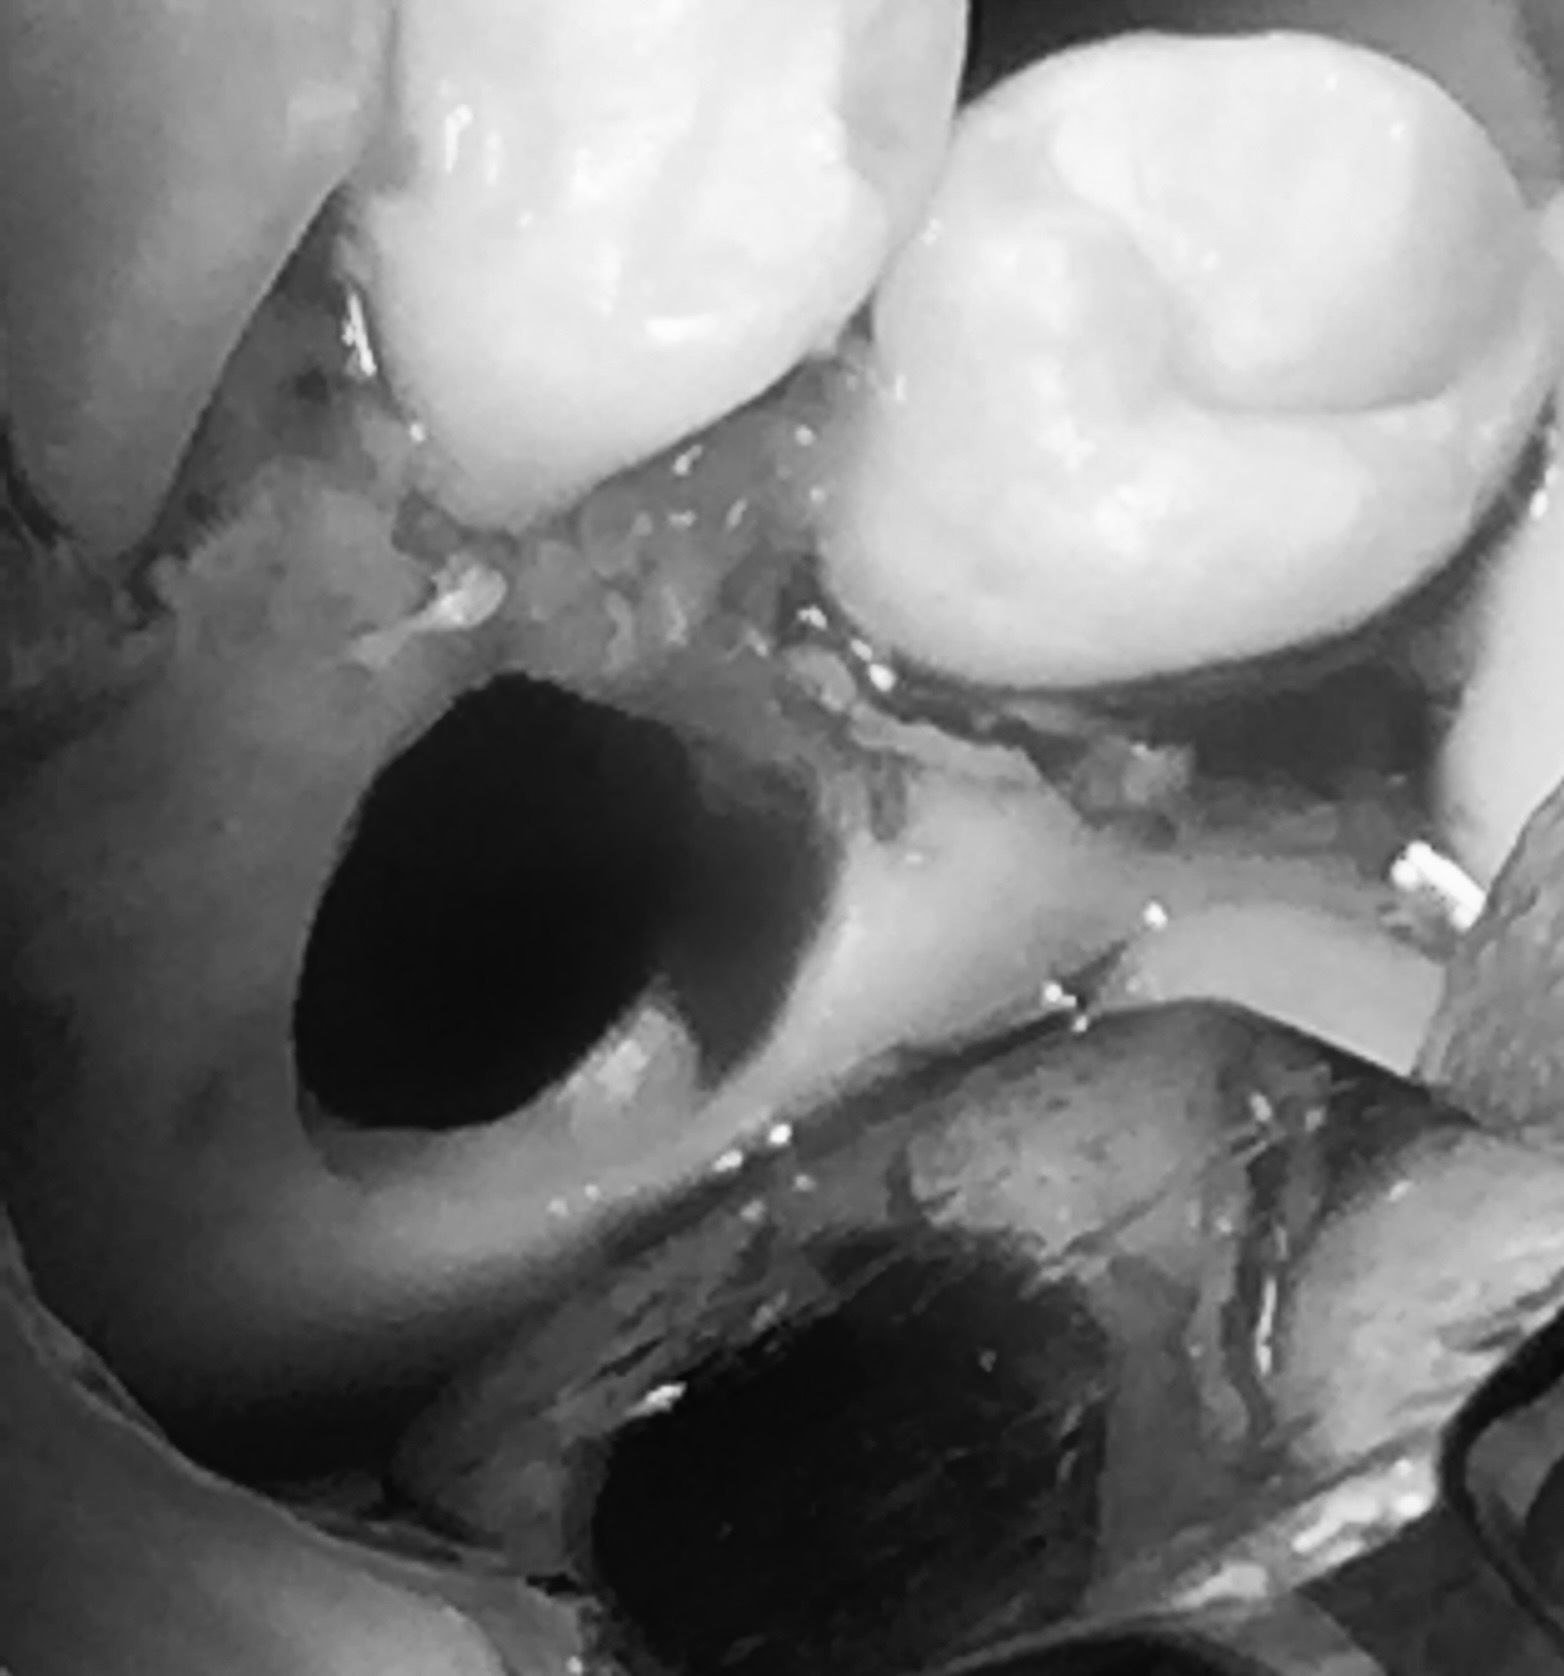

Rimozione di una cisti e agganciamento di un canino superiore incluso

Cisti che impedisce al canino di allinearsi

Rimozione della cisti e agganciamento del canino

Il canino viene trascinato nella posizione corretta

Il canino perfettamente allineato